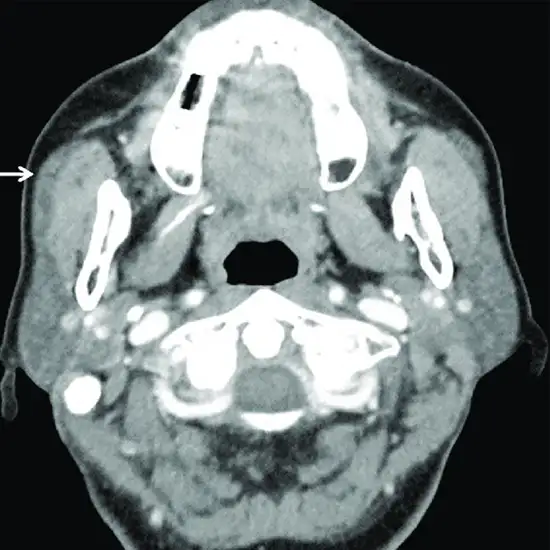

MRI sialography is the magnetic resonance imaging study of salivary glands. The technique is a non-invasive, painless and accurate procedure in detecting main ducts and intraglandular branches of the salivary glands.

Salivary gland calculi and salivary duct stenosis can be detected using MRI or MR sialography scans. This procedure does not require cannulation of the salivary duct openings. Also it does not expose the patient to radiation.

The MR sialography procedure is an effective diagnostic tool having sensitivity of 91% and a specificity of 94%-97% for calculi detection in non-dilated salivary ducts. For ductal stenosis, a sensitivity of 100% and specificity of 93%-98% is seen. For chronic sialadenitis, the specificity is 98% and sensitivity of 70%.